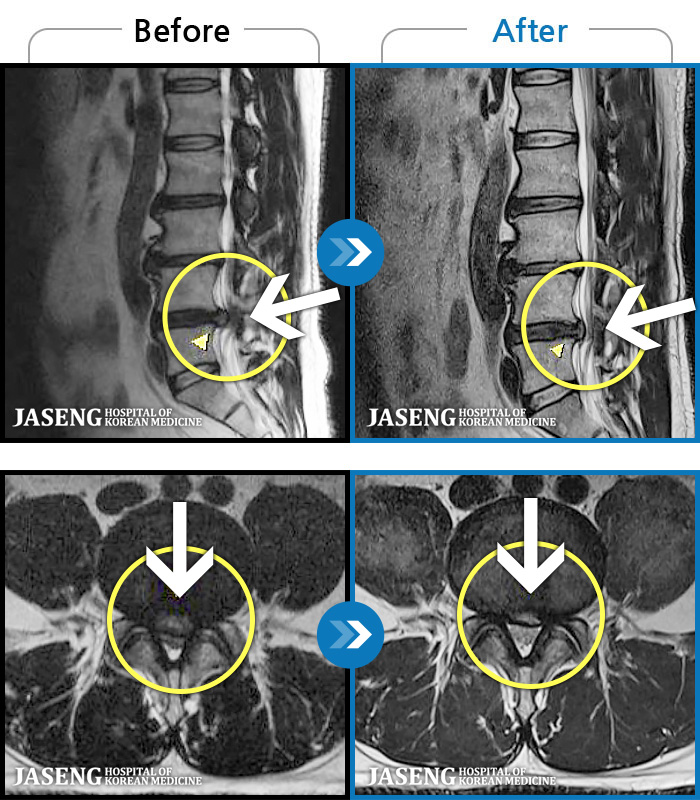

ȯںп Ǹ  ǿ ԿǾ, ο ġ ۿ  Ƿ ġḦ Ͻñ ٶϴ.   | ||||

ȯںп  Ǹ   ǿ ԿǾ, ο  ġ  ۿ     Ƿ   ġḦ Ͻñ ٶϴ.